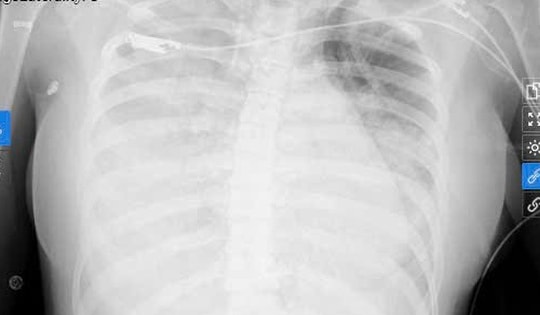

Chỉ với triệu chứng như cảm cúm, nữ sinh được phát hiện nhiễm liên cầu khuẩn nhóm A nguy kịch

Một nữ sinh 22 tuổi suýt mất mạng vì sốc nhiễm khuẩn do liên cầu khuẩn nhóm A. Nhờ sự điều trị tích cực từ các y bác sĩ của BVĐK Đức Giang, bệnh nhân đã vượt qua nguy kịch và hồi phục kỳ diệu.